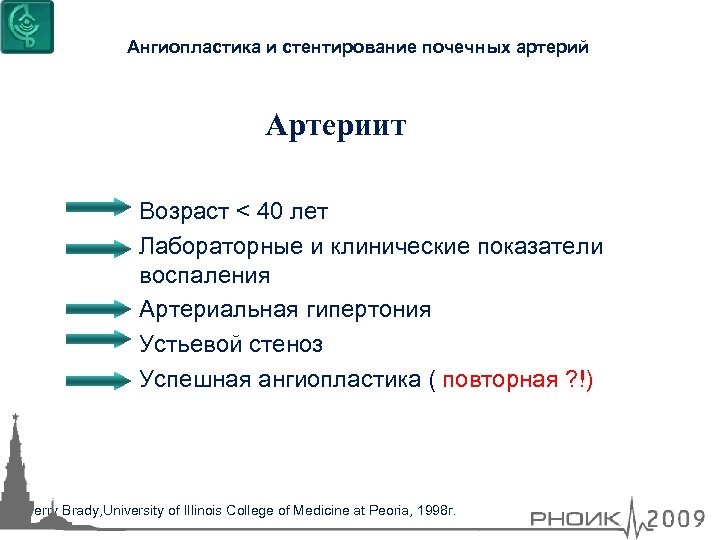

Ангиопластика и стентирование почечных артерий Артериит Возраст < 40 лет Лабораторные и клинические показатели воспаления Артериальная гипертония Устьевой стеноз Успешная ангиопластика ( повторная ? !) Terry Brady, University of Illinois Сollege of Medicine at Peoria, 1998 г.

Ангиопластика и стентирование почечных артерий Артериит Возраст < 40 лет Лабораторные и клинические показатели воспаления Артериальная гипертония Устьевой стеноз Успешная ангиопластика ( повторная ? !) Terry Brady, University of Illinois Сollege of Medicine at Peoria, 1998 г.